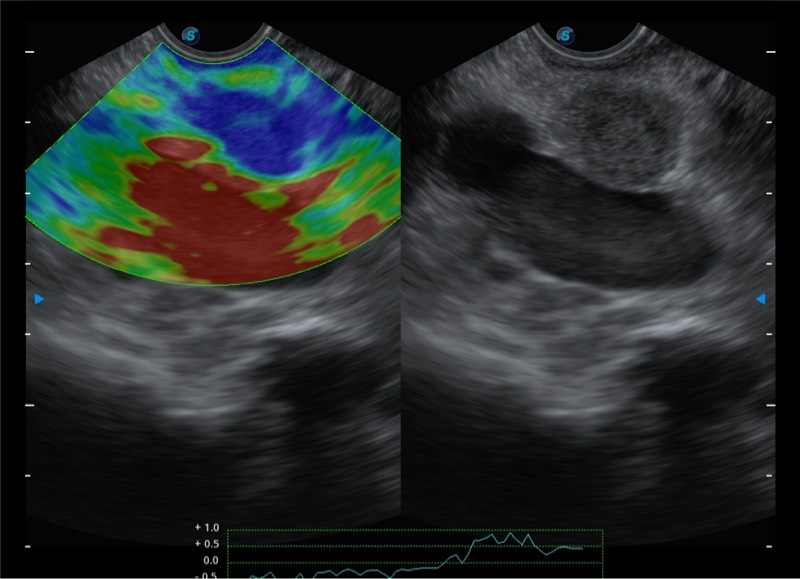

基于二十年的超声技术积累,乐玩lewin国际提供了最新一代的独立超声主机,在提供高质量图像的同时满足多学科使用。具备常见多普勒技术并提供弹性成像、声学造影等高端影像技术。新一代传感器具有更强的抗干扰能力并减少图像伪影。

4-12MHZ宽频输出